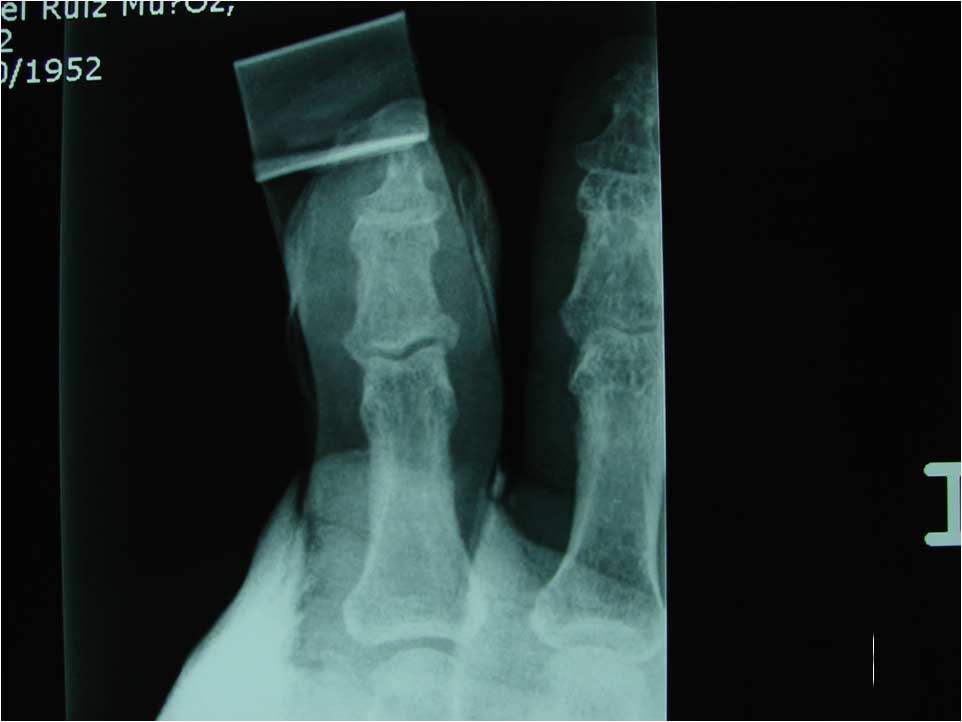

Caso 5